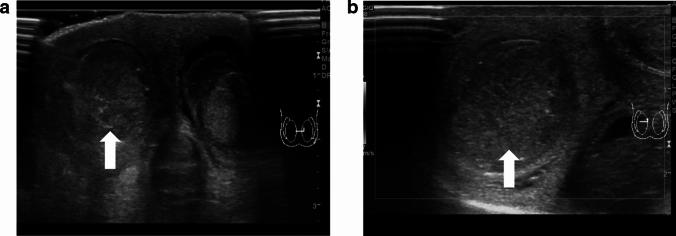

Testicular torsion is a urological emergency caused by the loss of testicular tissue due to ischemic damage. Rapid diagnosis and urgent treatment play a crucial role in the management of testicular torsion. Manual detorsion can be performed at the bedside, thereby reducing the duration of ischemia. Recent studies have reported the use of point-of-care ultrasonography for diagnosing testicular torsion; however, no review article has focused on the ultrasonographic findings pertaining to manual detorsion. This review describes the diagnosis of testicular torsion and the ultrasonographic indications for manual detorsion. Spermatic cord twisting or the whirlpool sign, absence of or decreased blood flow within the affected testis, abnormal testicular axis, abnormal echogenicity, and enlargement of the affected testis and epididymis due to ischemia are the sonographic findings associated with testicular torsion. The following findings are considered indications for manual detorsion: direction of testicular torsion, i.e., inner or outer direction (ultrasonographic accuracy of 70%), and the degree of spermatic cord twist. The following sonographic findings are used to determine whether the treatment was successful: presence of the whirlpool sign and the degree and extent of perfusion of the affected testis. Misdiagnosis of the direction of manual detorsion, a high degree of spermatic cord twisting and insufficient detorsion, testicular compartment syndrome, and testicular necrosis were found to result in treatment failure. The success of manual detorsion is determined based on the symptoms and sonographic findings. Subsequent surgical exploration is recommended in all cases, regardless of the success of manual detorsion.

睾丸扭转是一种泌尿外科急症,由缺血性损伤导致睾丸组织丧失引起。快速诊断和紧急治疗在睾丸扭转的管理中起着至关重要的作用。床边手动复位可减少缺血持续时间。最近的研究报告了使用即时超声检查来诊断睾丸扭转,但没有综述文章专门关注手动复位的超声表现。本文描述了睾丸扭转的诊断和手动复位的超声指征。精索扭曲或漩涡征、受累睾丸内无血流或血流减少、睾丸轴异常、回声异常以及缺血引起的受累睾丸和附睾增大是与睾丸扭转相关的超声表现。以下发现被认为是手动复位的指征:睾丸扭转的方向,即内旋或外旋(超声准确性为 70%)和精索扭转的程度。以下超声表现用于确定治疗是否成功:漩涡征的存在以及受累睾丸的灌注程度和范围。手动复位方向的误诊、精索扭转程度高和复位不足、睾丸间隔综合征和睾丸坏死均导致治疗失败。手动复位的成功与否取决于症状和超声表现。无论手动复位是否成功,都建议进行后续的手术探查。